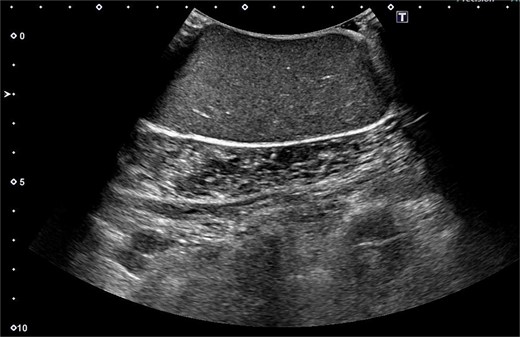

A 61-year-old man presented to the outpatient breast clinic with a painless lump in his right pectoral region. The lump was first noticed 40 years earlier at the size of a small fingertip and gradually increased. The lump was approximately 90 mm in diameter, well-defined, and dome-shaped. The overlying skin appeared glossy with no visible puncta (Fig. 1). Erythema or bruising was not observed. On palpation, the lump was non-tender and doughy with no localized temperature increase. It was not fixed to underlying tissue. On ultrasound imaging, the lump showed a hypoechoic and well-circumscribed oval mass containing variable echogenic foci and filiform anechoic areas without color Doppler signals (Fig. 2). The lump was located in the subcutaneous fat layer, with extensive dermal apposition. In sagittal magnetic resonance imaging (MRI), the lump showed a unilocular and well-defined cystic mass (70 × 40 × 90 mm) (Fig. 3A and B). The cyst content showed an isointense signal relative to the muscle with no enhancement in the sagittal enhanced T1-weighted image (Fig. 3A), and a hyperintense signal in the T2-weighted image (Fig. 3B). Ultrasound-guided percutaneous CNB was performed, and six core specimens containing cystic walls ware sampled (Fig. 4A). The cystic wall was lined with mature stratified squamous epithelium with a granular layer and did not contain an adnexal structure (Fig. 4B). In addition, many laminated or basket-woven keratin layers were sampled. These findings ware consistent with those of an epidermal cyst. The mass was excised under general anesthesia. The mass was well-defined and did not adhere to the surrounding structures, except for a portion of the CNB (Fig. 5). The mass was easily excised. The formalin-fixed mass was covered with a thick white fibrous capsule (Fig. 6A), which was filled with grey substances, such as bean curd residue, in the cross-section (Fig. 6B). After the removal of the contents, the internal surface of the capsule was crepey, and no nodules were observed (Fig. 6C). The definitive pathological diagnosis was an epidermal cyst without any malignancy. The adhesive region revealed keratin, which flowed outside the cyst, and a granulomatous response to keratin with multinucleated giant cells (Fig. 7). No complications or recurrences were observed during the one-year follow-up after surgery.

Ultrasound imaging showing hypoechoic and well-circumscribed oval mass containing variable echogenic foci and filiform anechoic areas.